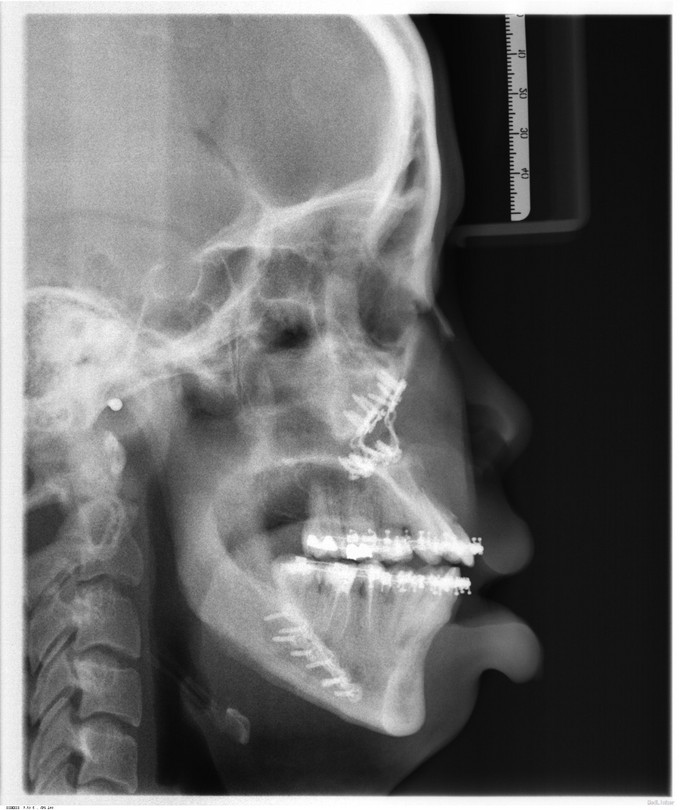

发现下颌前突、上颌后缩数年,于13年行正畸治疗。今为进一步治疗来我院就诊,门诊以"下颌前突、上颌后缩"收入院。

面部发育一般,中线左右对称,上中下比例不协调,上颌后缩,下颌前突,颏顶点正中。左侧颞下颌关节无弹响无疼痛动度正常,右侧颞下颌关节无弹响无疼痛动度正常。张口度4.0cm,开口型正常。上下牙弓关系协调,前牙反合约0.6cm,龋齿无,牙周病无。

入院诊断:1.下颌前突2.上颌后缩3.偏颌畸形,出院诊断: 1.下颌前突2.上颌后缩3.偏颌畸形4.双侧上颌窦粘液囊肿,全麻下行“上颌LefortI型颌骨前徙术+骨内坚固内固定术+双侧下颌升支矢状劈开后退术+双侧下颌骨去骨皮质术+骨内坚固内固定术+双侧邻近瓣转移修复术+双侧上颌窦粘液囊肿摘除术”